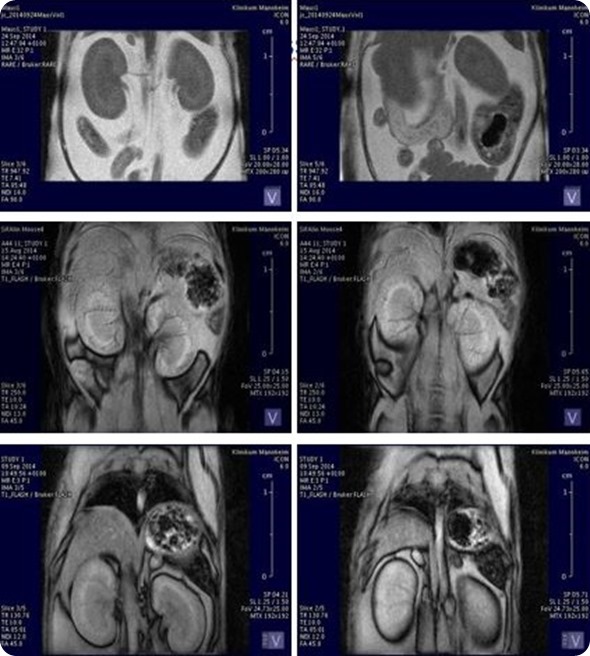

ICON: Organ volumetry and tissue characteristics. Image Credit: Bruker BioSpin Group

In the case of the MRI, it's mostly a combination with the PET system, which allows a better contrast in the brain or body and enables us to see the soft tissues better or to differentiate better between them in the body.